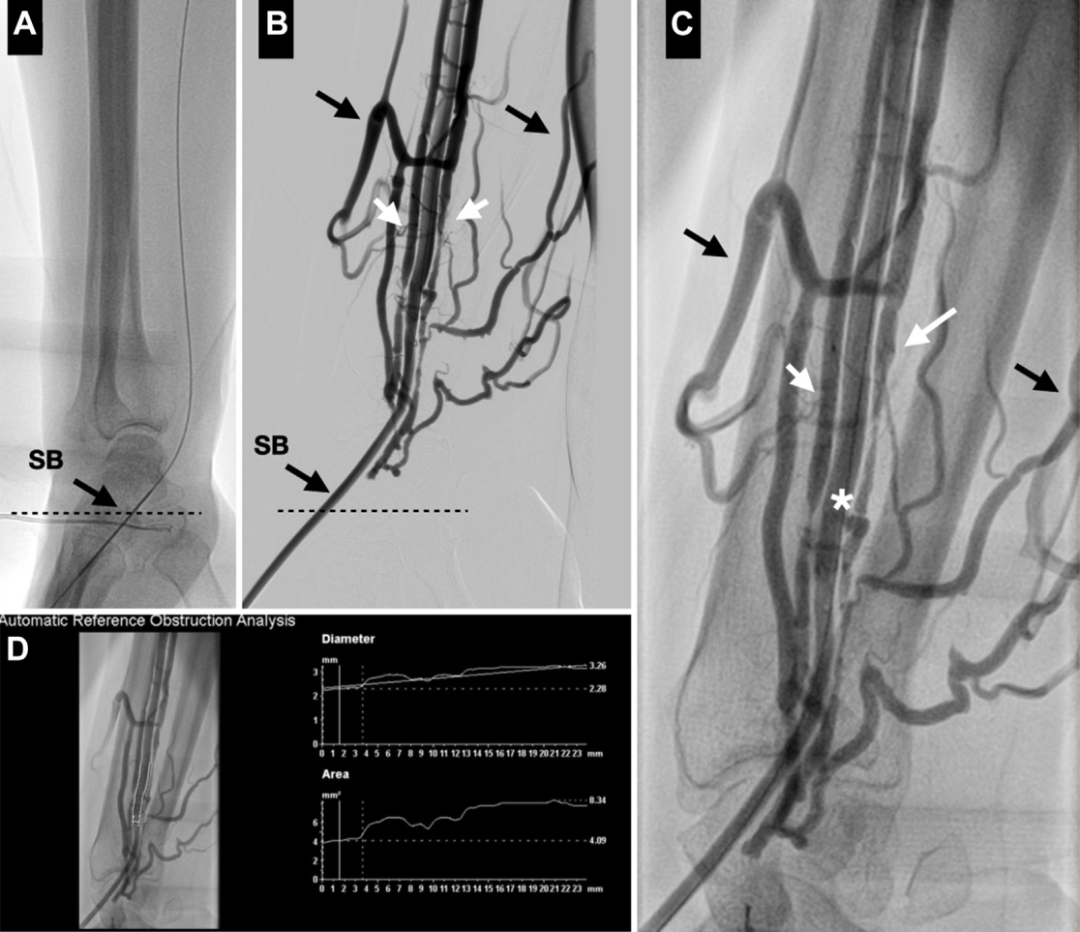

与患者讨论后,决定对LAD、IM和LCx进行PCI。二十天后,患者接受了成功的IVUS引导下PCI,在无保护左主干、LAD近端和IM中段植入了支架,并在LCx近端使用药物球囊进行了血管成形术(图2)。

图2.PCI手术过程造影图像

基线血管造影显示桡动脉通畅,同时可见增粗扩张的桡深静脉与浅表的头静脉和贵要静脉相通(图5)。为达到最大血管舒张,动脉内注射硝酸甘油后,获取了多幅血管造影图像,以评估桡动脉的合适尺寸并确定AVF瘘口的确切位置。

根据初始超声测量结果,选择了一枚冠脉覆膜支架(3.5×21mm,ePTFE覆膜),将覆膜支架置于瘘口部位,并以标称压力(11atm)扩张,实现即刻封堵。

使用3.5×15mm非顺应性球囊进行了再次扩张,特别是在支架边缘,以确保完全隔绝。最终血管造影显示桡动脉完全通畅,无静脉循环显影,表明AVF闭合成功(图6)。

图5.通过右侧远端桡动脉(dTRA)的基线血管造影

(A)通过20G针,插入0.025in导丝,植入6F桡动脉。(B,C)基线造影显示静脉系统明显显影,近端静脉循环扩张,使桡深静脉(白色箭头)与浅静脉系统(头静脉和贵要静脉;黑色箭头)之间形成连通。(D)注射硝酸甘油后,验证桡动脉的确切直径,以便选择合适尺寸和长度的覆膜支架(最小直径2.3mm,最大直径3.2mm)。星号指示AVF瘘口。

图6.AVF闭合手术步骤详解

(A)基线图像。黑色箭头指示增粗扩张的前臂浅静脉、头静脉和贵要静脉。(B)在瘘口(白色箭头)放置覆膜支架。(C)覆膜支架在12atm压力下扩张。(D至F)使用非顺应性球囊进一步扩张,特别是在覆膜支架边缘以确保覆膜支架完全贴壁。(G)已释放覆膜支架的增强影像图像。(H)最终血管造影图像显示AVF瘘口完全被封堵。